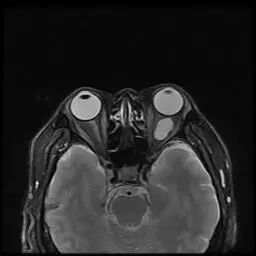

图片

眼部影像

如何让手术创伤更小?宋艳向医学3D打印创新研究中心发出了会诊邀请。中心根据小王的眼部影像学数据,对肿瘤及其周边组织进行了可视化重建分析,为他建立起左眼的3D模型。